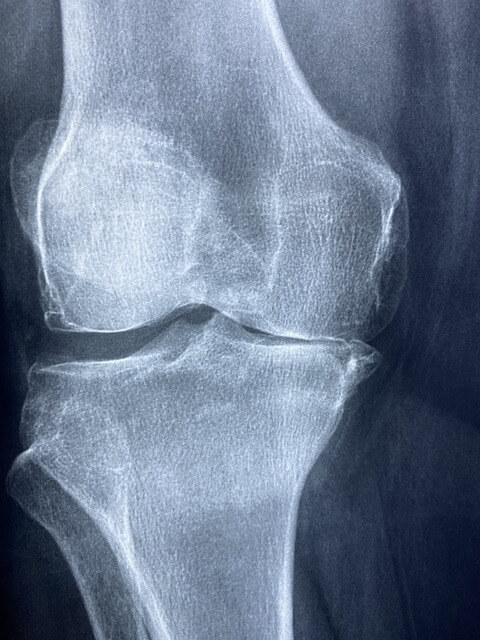

● 갑작스러운 심한 통증: 주로 밤에 시작되며, 엄지발가락이나 발목, 무릎 등에서 발생합니다. 통증은 매우 강하고, 관절이 붓고 뜨겁게 느껴집니다.

● 발적 및 부종: 염증이 생기면 관절 주변이 붉고 부풀어 오릅니다.